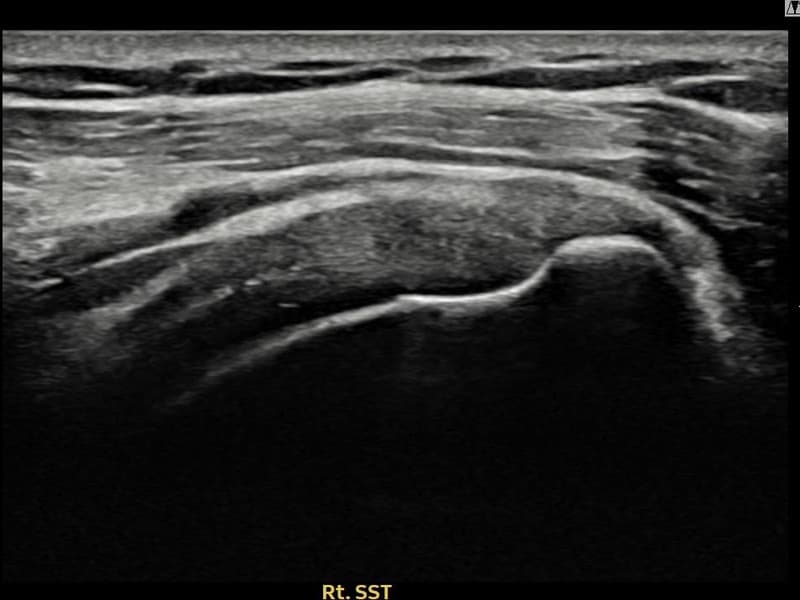

After

시술 전 초음파 측정 결과 파열 크기는 10mm × 4mm (힘줄 두께의 약 40% 결손)로 확인되었습니다. 시술 전 초음파에서 우측 극상근건 관절면측의 에코 불균질성과 힘줄 내 결손 소견이 확인되었습니다. 시술 후 초음파에서 힘줄 에코 패턴이 균질하게 회복되고 연속성이 정상화된 것이 관찰되었습니다.

60대 여성 환자분으로, 수년간 무릎 통증으로 보행이 불편한 상황에서 어깨까지 아프기 시작하여 일상 전반이 힘들어진 상태였습니다. 초음파 검사에서 우측 극상근건 관절면측의 부분파열이 확인되었으며, 전신 상태와 활동 수준을 고려하여 부담이 적은 비수술 축소봉합술을 선택하였습니다. 시술은 30분 이내에 완료되었고 당일 귀가하셨으며, 보조기 착용 4주 후 천천히 가동 범위를 늘려나갔습니다. 시술 10주 후 추적 초음파에서 극상근건 연속성이 안정적으로 회복된 것이 확인되어 통증 없이 일상 복귀에 성공하셨습니다.